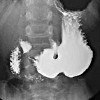

Рентгенография желудка ребенку

Рентгенография желудка ребенка проводится после приема специального рентгеноконтрастного препарата. У детей первого месяца жизни используется водорастворимый контраст (гастрографин, верографин, уростраш), у детей старшего возраста - суспензия сульфата бария. У недоношенных детей, детей без рефлексов сосания и глотания, стеноза пищевода, рвоты вводят в желудок с помощью контрастного вещества через трубку. Анализируя полученные рентгеновские снимки, оценивают гибкость стенок желудка, его форму, размеры и контуры, тонус, перистальтику, функцию эвакуации и состояние двенадцатиперстной кишки. Рентгенография желудка ребенка проходит натощак.